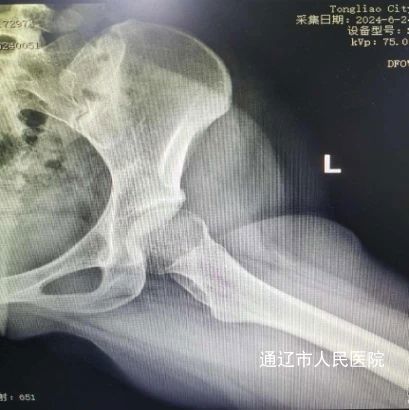

术前影像:

患者张某,女性,24岁,2年前开始出现左侧髋关节肿痛伴活动受限,严重影响日常生活,门诊经过查体及髋关节半髋磁共振检查诊断为:髋臼撞击综合征合并盂唇撕裂。由于患者年纪较轻,左侧髋关节撞击导致髋臼盂唇损伤,长期疼痛,胡中申主任医师带领其关节外科团队对该病例进行详细周全地讨论,综合评估患者病情并得到家属同意后,建议实施髋关节镜手术治疗。